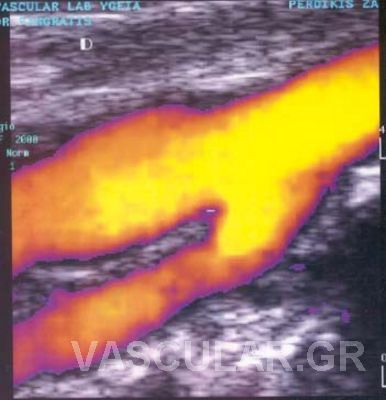

Ç Triplex åîÝôáóç ãßíåôáé áêñéâþò üðùò êáé ç Duplex åîÝôáóç ìå ôçí äéáöïñÜ üôé ç áéìáôéêÞ ñïÞ áðåéêïíßæåôáé Ýã÷ñùìç åíôüò ôïõ áããåßïõ êáé óõãêåêñéììÝíá ç öõãüêåíôñïò áéìáôéêÞ ñïÞ ( áðü ôçí êáñäéÜ) Ý÷åé êùäéêïðïéçèåß ìå êüêêéíï ÷ñþìá åíþ ç êåíôñïìüëïò ñïÞ (ðñïò ôçí êáñäéÜ) ìå ìðëå ÷ñþìá.

Ôï åðéðëÝïí äçëáäÞ óôïé÷åßï ðïõ ðñïóöÝñåé ç Triplex åîÝôáóç åßíáé ç Üìåóç áðåéêüíéóç ôïõ áõëïý ôïõ áããåßïõ ìÝóù ôçò åéêüíáò ôçò áéìáôéêÞò ñïÞò . Ç ìåãÜëç äå äéáöïñÜ ôçò Ýãêåéôáé óôçí éêáíüôçôá íá äåßîåé ôï spatial orientation ôçò áéìáôéêÞò ñïÞò. Èåùñåßôáé åðßóçò ðéü áîéüðéóôç ìÝèïäïò ãéá íá áíáäåßîåé åðéèñüìâùóç ÁèçñùìáôéêÞò ÐëÜêáò Þ ðñüóöáôï èñüìâï åðß ôïõ ôïé÷þìáôïò , ðïõ ëüãù ôçò öýóçò ôïõ õëéêïý êáé ïìïßùí õðåñç÷ïãñáöéêþí ÷áñáêôçñéóôéêþí ìå ôï áßìá äåí áðåéêïíßæåôáé óôïí Ýëåã÷ï ìå Duplex åîÝôáóç